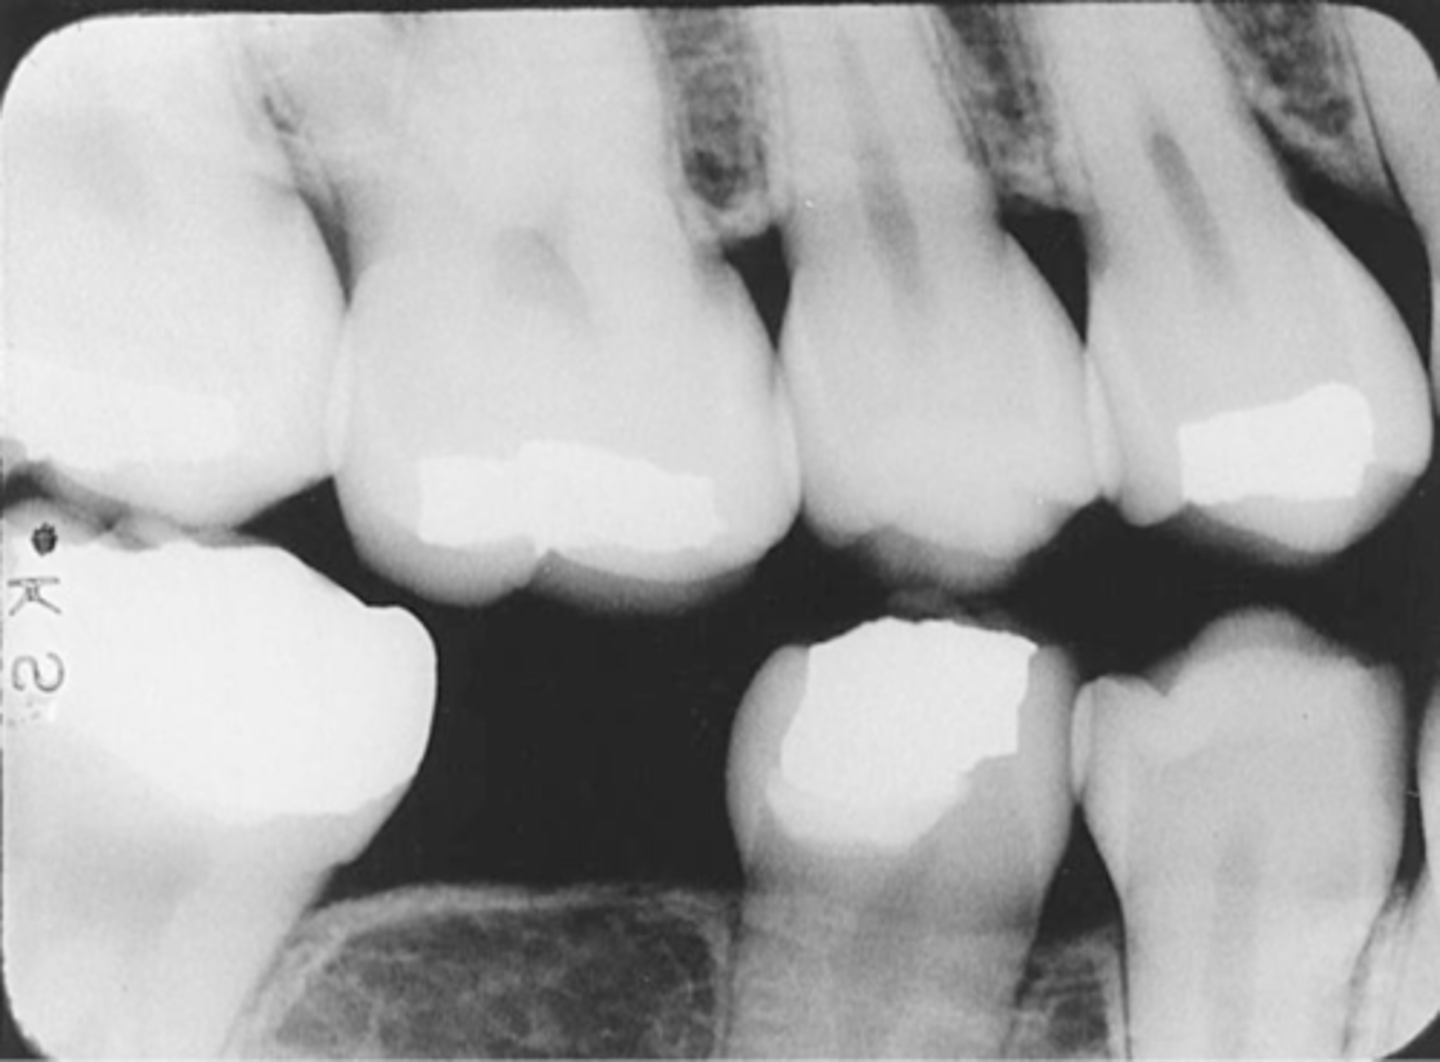

Incorrect Receptor Placement of Bite-Wing receptor

-May result in absence of specific teeth or tooth surfaces on an image, a tipped occlusal plane, overlapped interproximal contacts, or a distorted image, and rendering it undiagnostic

Incorrect Receptor Placement--Premolar Bite-Wing

-Distal surfaces of canines are not visible on the image

-Receptor was positioned too far posteriorly in the mouth; front edge of the receptor was not placed at the midline of the mand. canine.

Incorrect Receptor Placement-->Molar Bite-Wing

-Third molar regions are not visible

-Receptor was too far anteriorly in the mouth; front edge of the receptor was not placed at the midline of the mand. 2nd premolar

-To prevent Always center on the mand. 2nd molar, even with 3rd molars are not present